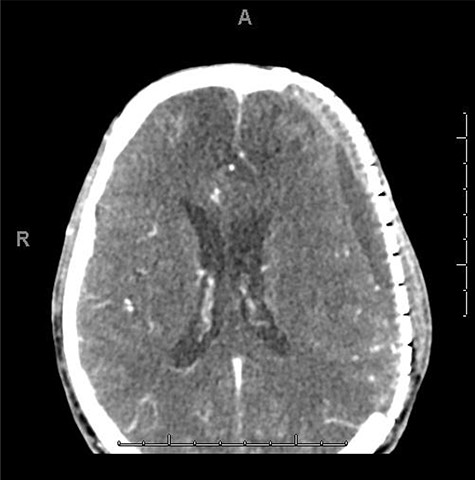

He had a significant recovery, to the point where he was awake with mild right paresis. He was following commands briskly but remained nonverbal. On hospital day 26, he developed neurological deterioration with decreased mental status and worsening right hemiparesis. Clinical examination noted pronounced new indentation of his hemicraniectomy flap site. CT head showed a rightward shift away from the craniectomy site and impending herniation (Fig. 4).

CT head POD26 from craniectomy demonstrating findings consistent with SSFS.

He was positioned in Trendelenburg position and infused with intravenous fluids with some improvement in his symptoms. Based on his clinical and radiographic picture, SSFS was suspected. He was taken to the operating room for an emergency left cranioplasty, with a preformed fronto-temporo-parietal titanium mesh.